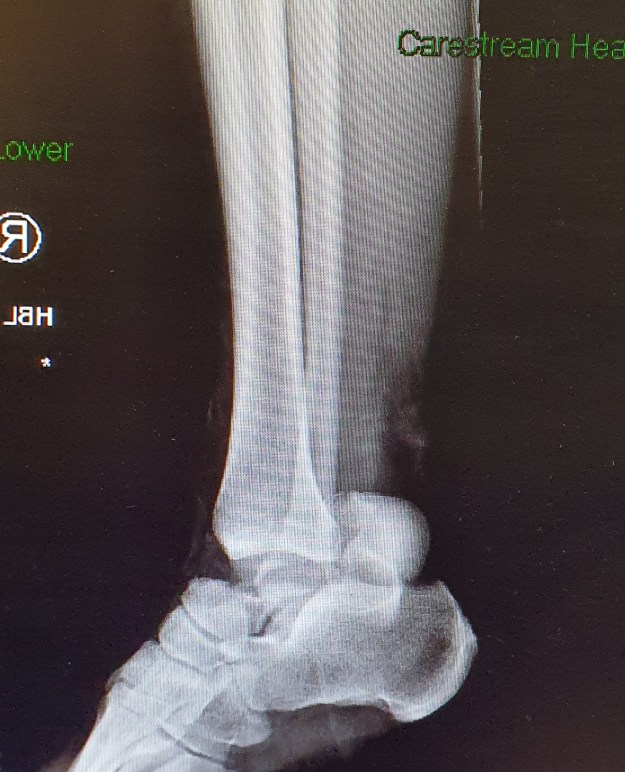

X-Ray of my right ankle, showing that my Talus (ankle bone) has broken. The bone is now lodged near my heel. This X-Ray is prior to surgery

The accident shifted my Talus from its normal position to the back of my heal, meaning urgent surgery was required to ensure that I would not lose my foot. The surgery meant that until today, the 14 of May, I have been unable to get out of bed, get to a computer and sit comfortably enough to work.